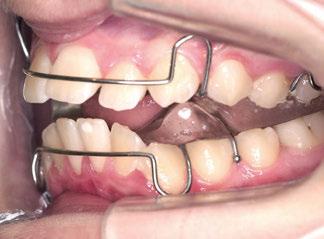

En este artículo se describe el caso de una niña de 9/2 años con síndrome de Clase II por hipoplasia mandibular que recibió tratamiento en dos fases: una primera, ortopédica, para estimular el crecimiento mandibular mediante aparatología funcional; y una segunda fase, ortodóncica, con la colocación de brackets de autoligado pasivo de la técnica USS (Universal Smile System) de prescripción variable para el desarrollo y coordinación de las arcadas dentarias.

Tras la terminación de la fase ortopédica, se continuó con la colocación de los brackets

mencionados anteriormente. La prescripción de estos fue de alto torque en los incisivos superiores y en los cuatro caninos, y de bajo en los incisivos inferiores. Tras 12 meses desde la colocación de los brackets y una vez conseguida la normalización de las relaciones oclusales, se colocaron unos retenedores fijos de canino a canino en ambas arcadas de acero trenzado de 6 hilos (.017” superior y .019” inferior) y un guarda de contención nocturna hasta la terminación del crecimiento puberal.

Transcurridos 7 meses, se sustituyó por un Twin Block para un segundo y definitivo avance (figuras 12 a 16).

Este último aparato funcional se mantuvo en boca durante 8 meses, tras haber conseguido la mejoría esperada en cuanto al aspecto facial (figura 17) y las relaciones oclusales (figuras 18 a 22). La mordida abierta lateral producida es fácilmente solucionable en la siguiente fase de tratamiento.

Con el cementado de los brackets de la técnica Universal Smile System

(USS), como se aprecia en las figuras 23 a 25, comienza la segunda fase de tratamiento. Esta duró tan solo 12 meses debido a que gran parte de las relaciones oclusales habían mejorado durante la etapa anterior. Los resultados finales del tratamiento se observan en las figuras 26 a 30 , con la corrección de la clase molar y canina, el resalte y la sobremordida, el centrado de las líneas 1/2 y la curva de Spee. La mejoría en la macro, mini y microestética facial se aprecia en las figuras 31 a 33 , a pesar de la evidente desviación del mentón hacia